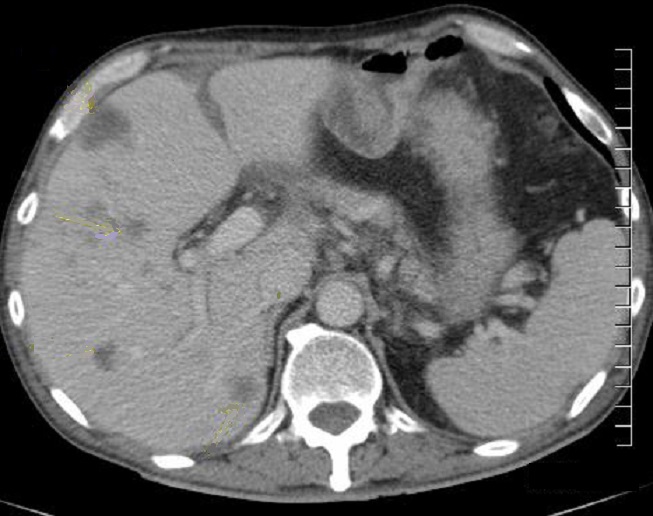

Image TDM

de abces du foie : Aspect TDM de abces du foie est

variable : lesion en apparence peripherique de hyperdensite

et a central hypodense s'observe souvent dans abces amibien . Ce qui peut en presence de

gas ( 20% de gas ) . Aspect en cloisone ou multiple

loculaire , bien definie " cluster sign" peut

se retrouve dans l'abces a pyogenes. En cas de TDM

plus de contrast intraveineuse , image de double de cible "double

target sign" peut en voyait .

Aspect radiologique TDM d'une abces

a pyogenes multi loculaire du foie en realisee sous forme de

grappe "cluster sign " . |

|

Image TDM d'une abces du foie en coupe

coronale . Aspect de la lesion est hypodense

multi loculaire se situe au foie gauche . Image

radiologique TDM encoupe coronal , aspect

radiologique en susgeste du abces a pyogenes |